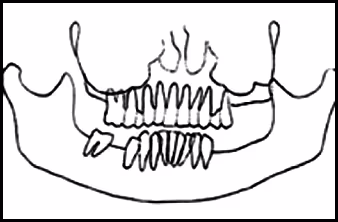

These figures demonstrate the effects of twisting. Elongation of left mandible, reduction in size of teeth on the opposite side, occlusal plane canting and pronounced tooth overlap on the same side.

Figure 43A. Panoramic Image.

Figure 43B. Panoramic Schematic.